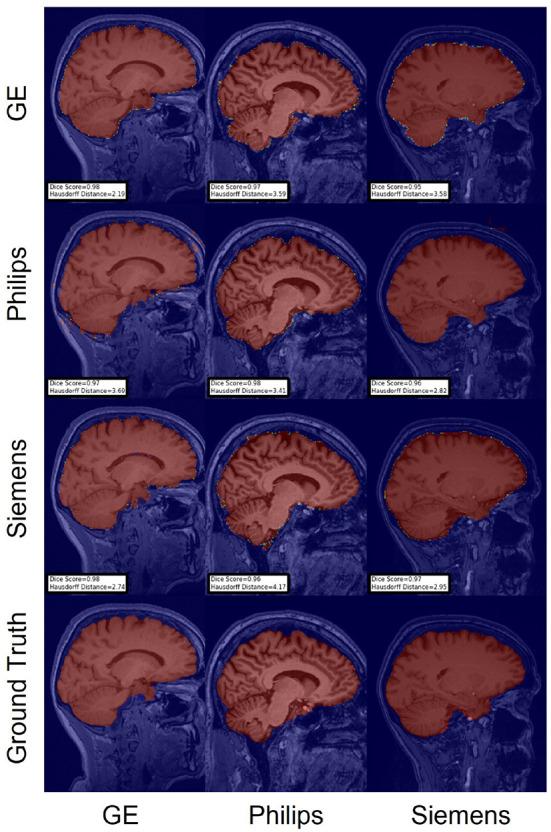

Accurate brain segmentation is critical for magnetic resonance imaging (MRI) analysis pipelines. Machine-learning-based brain MR image segmentation methods are among the state-of-the-art techniques for this task. Nevertheless, the segmentations produced by machine learning models often degrade in the presence of expected domain shifts between the test and train sets data distributions. These domain shifts are expected due to several factors, such as scanner hardware and software differences, technology updates, and differences in MRI acquisition parameters. Domain adaptation (DA) methods can make machine learning models more resilient to these domain shifts. This paper proposes a benchmark for investigating DA techniques for brain MR image segmentation using data collected across sites with scanners from different vendors (Philips, Siemens, and General Electric). Our work provides labeled data, publicly available source code for a set of baseline and DA models, and a benchmark for assessing different brain MR image segmentation techniques. We applied the proposed benchmark to evaluate two segmentation tasks: skull-stripping; and white-matter, gray-matter, and cerebrospinal fluid segmentation, but the benchmark can be extended to other brain structures. Our main findings during the development of this benchmark are that there is not a single DA technique that consistently outperforms others, and hyperparameter tuning and computational times for these methods still pose a challenge before broader adoption of these methods in the clinical practice.

准确的脑部分割对于磁共振成像(MRI)分析流程至关重要。基于机器学习的脑磁共振图像分割方法是完成这项任务的最先进技术之一。然而,在测试集和训练集数据分布之间存在预期的域偏移时,机器学习模型生成的分割结果往往会退化。由于多种因素,如扫描仪硬件和软件差异、技术更新以及MRI采集参数的差异,这些域偏移是预期会出现的。域适应(DA)方法可以使机器学习模型对这些域偏移更具弹性。本文提出了一个基准,用于使用从不同供应商(飞利浦、西门子和通用电气)的扫描仪跨站点收集的数据来研究脑磁共振图像分割的DA技术。我们的工作提供了标记数据、一组基线模型和DA模型的公开可用源代码,以及一个用于评估不同脑磁共振图像分割技术的基准。我们应用所提出的基准来评估两项分割任务:去颅骨;以及白质、灰质和脑脊液分割,但该基准可以扩展到其他脑结构。我们在开发此基准过程中的主要发现是,没有一种DA技术能始终优于其他技术,并且在这些方法更广泛地应用于临床实践之前,这些方法的超参数调整和计算时间仍然是一个挑战。